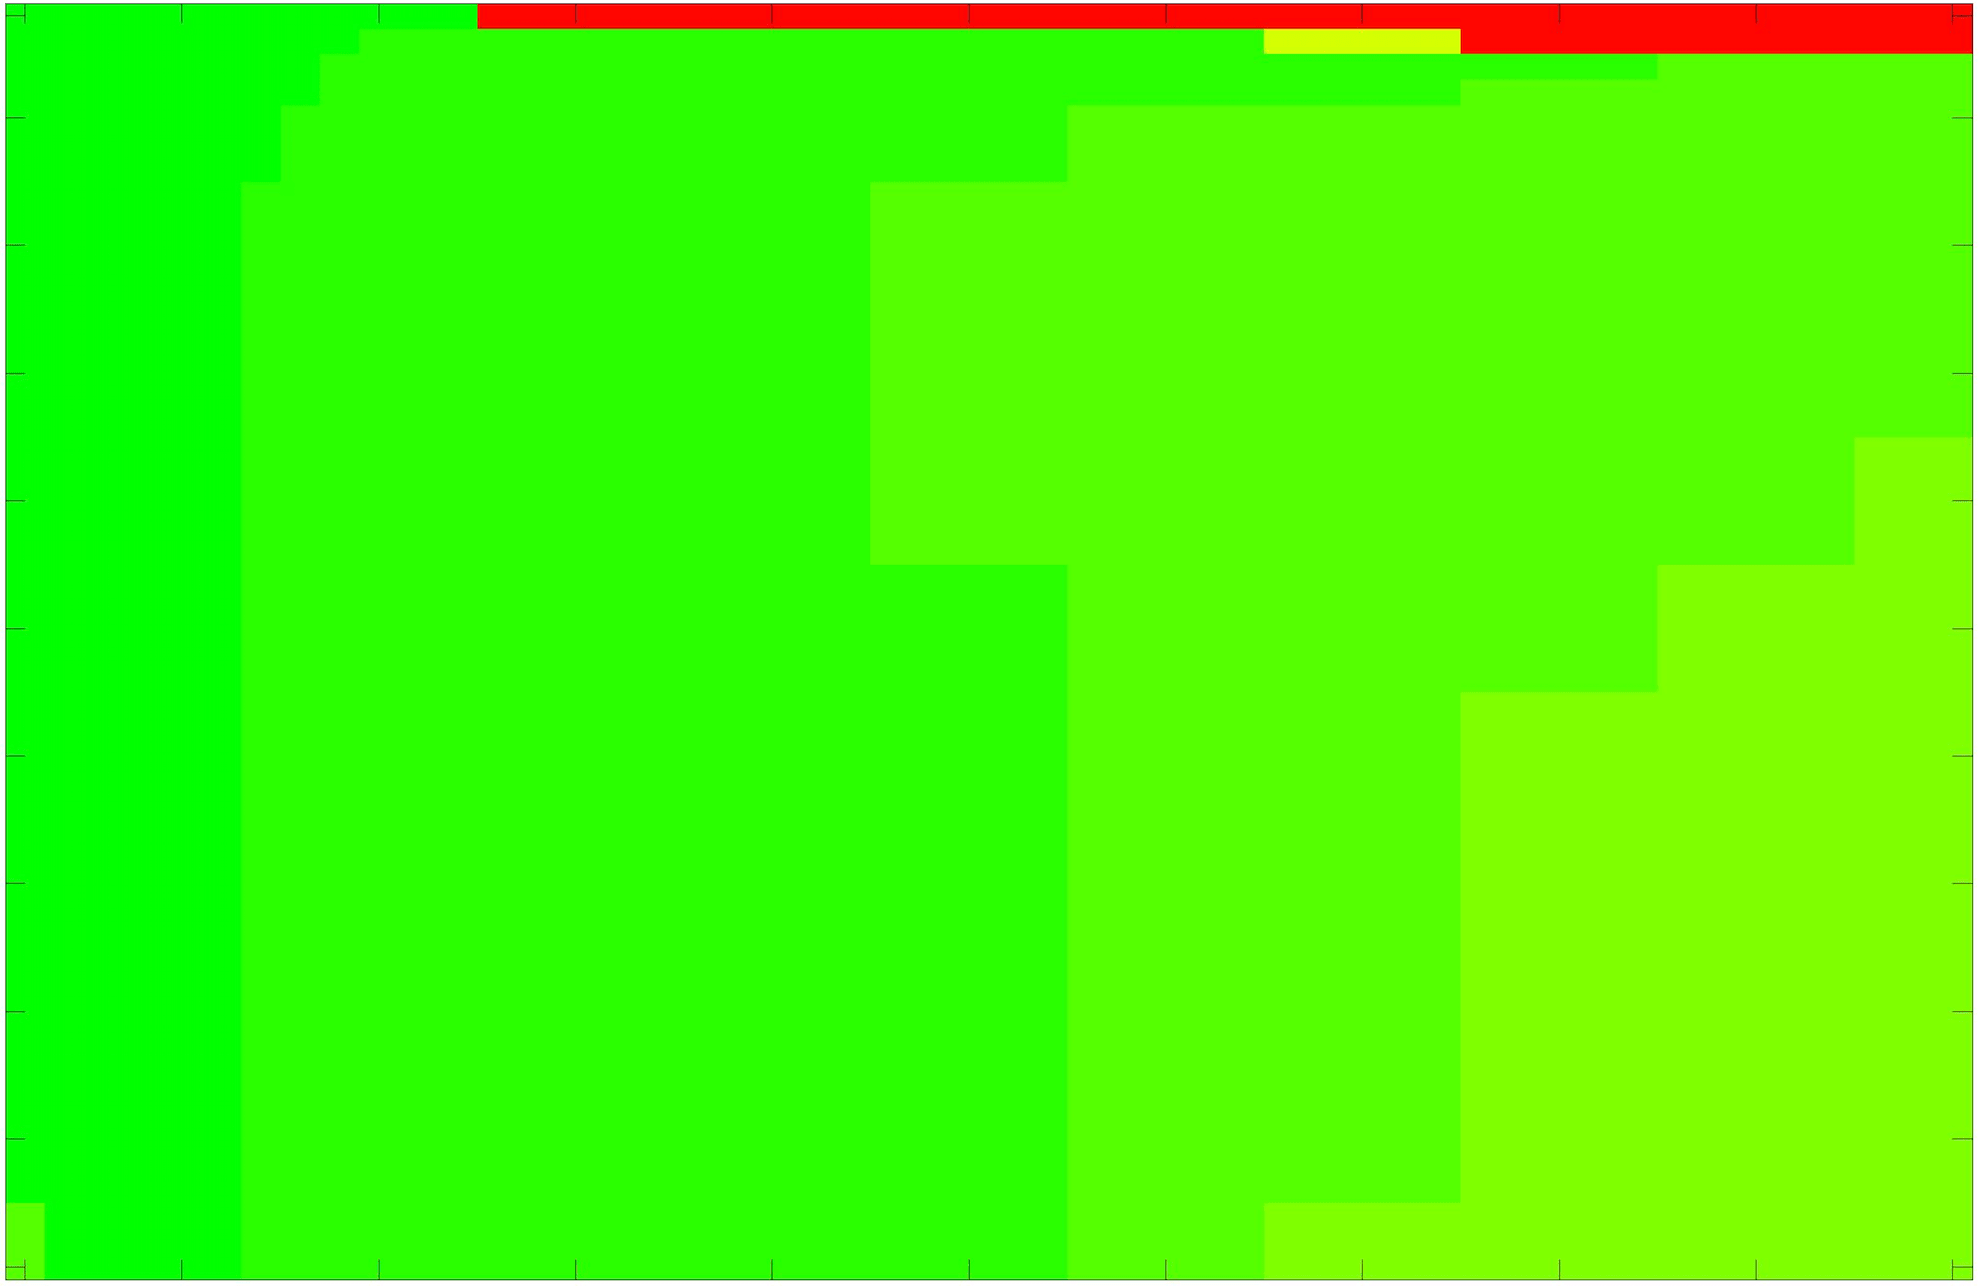

where refers to the number of points in the enclosed region. This takes values in the range , with higher TC values indicating a more accurate segmentation. In the following we will represent accuracy visually from red () to green (), with the intermediate scaling of colours used shown in Fig. 8. This will be particularly relevant in §7.2.

The TC values for the parameter sets are presented as heatmaps in Figs. 11–13. A heatmap is a convenient way to display accuracy results for hundreds of tests concisely. In Fig. 9 we give an example heatmap with the same axes used for those in Figs. 11–13. For each of the combinations of parameter values we give the TC value of the segmentation result and represent it by the appropriate colour. The corresponding colour scale is shown in Fig. 8. Qualitatively, the more green areas of the heatmap the more accurate the model is for a wider set of parameters. Example results for Test Image 5 when varying (with ) for the proposed model are given in Fig. 10. Here it can be seen what each accuracy result corresponds to visually.

Note. The axes have been removed from the heatmaps in Figs. 11–13 for presentational clarity. However, to be explicit, the axes used in all heatmaps are the same as those in Fig. 9.